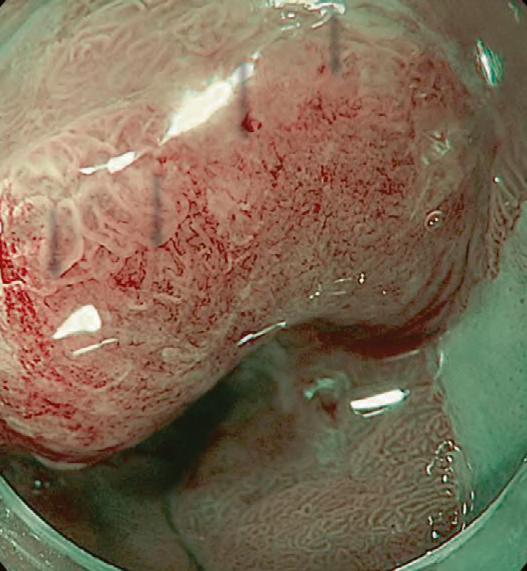

Between the late 1980s and early 1990s, research on image processing and analysis was conducted mainly by the National Cancer Center Hospital East and Olympus Group, which led to basic experiments on narrow band light imaging starting in 1994. As a result, a patent application was made in 1999, and a narrow band imaging (NBI) device (Olympus Co., Tokyo, Japan) was introduced commercially in 2006. Since the early 2000s, it has been demonstrated by a number of researchers that NBI is useful for early diagnosis of cancers of the oropharynx, hypopharynx, esophagus, stomach, and large intestine. A succession of similar techniques was later made public, and interpretation of the term “special light observation” began to differ among academic societies and research organizations. In view of this problem and the need to establish internationally applicable terminology for endoscopy, we proposed an object-oriented classification for endoscopic imaging in 2008. Basically, the concept was that endoscopic imaging can be divided into five categories: (1) conventional endoscopy (white light endoscopy (WLE)), (2) image-enhanced endoscopy (IEE), (3) magnified endoscopy, (4) microscopic endoscopy, and (5) tomographic endoscopy [1].

While NBI has spread and contributed to the standardization of diagnosis on a global level, our colleagues have worked tirelessly to further improve the quality of endoscopy. Over the last 15 years, owing to the development and worldwide spread of NBI, international classifications have been introduced in the field of gastric cancer, Barrett’s esophagus, and colorectal neoplasia.

The LASEREO system (FUJIFILM Co., Tokyo, Japan) based on laser endoscopy was developed for advanced IEE, including WLI, BLI, and LCI. LCI using short-wavelength narrow band laser light combined with white laser light is a new technique that enhances differences in red coloration through digital processing [2]. This enables LCI to visualize red lesions better by enhancing their intensity relative to whitish lesions, which appear whiter. Recently, a controlled, multicenter trial with randomization using minimization has reported that LCI is more effective than WLI for detecting neoplastic lesions in the pharynx, esophagus, and stomach [3].